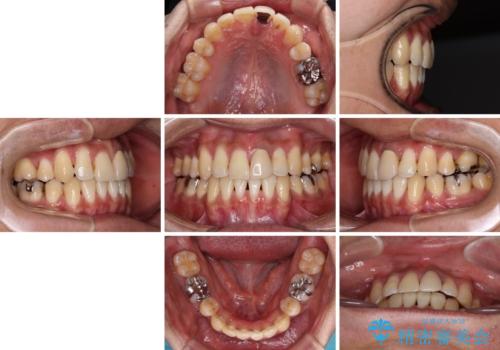

ワイヤー矯正と比較すると、八重歯が後方に傾斜した仕上がりとなりましたが、患者様ご希望のインビザラインにて十分な歯列を達成することができました。